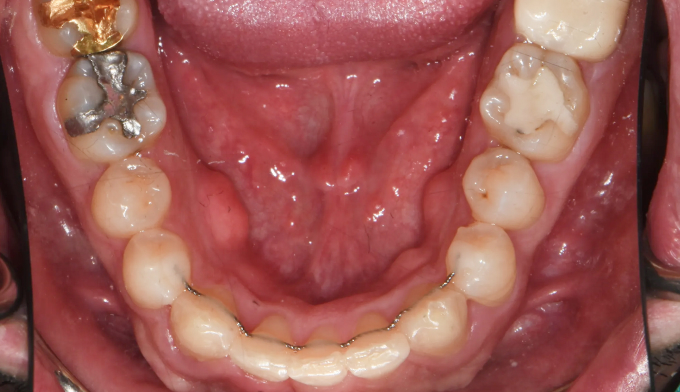

턱근육의 과활성은 교정치료를 어렵게 만드는 요인 중 하나입니다. 최대한 미소선에 맞추어 앞니를 배열하고 과개교합도 개선하였습니다. 턱근육의 이완을 돕고자 보톡스 치료도 동반하였습니다.

위 앞니 잇몸선의 비대칭도 관찰되어 잇몸절제술도 권유드렸으나 현재 상태에 만족하셔서 교정치료를 8개월만에 종료하였습니다.

길지 않은 기간이지만 한사람의 인상을 바꿀 수 있습니다.